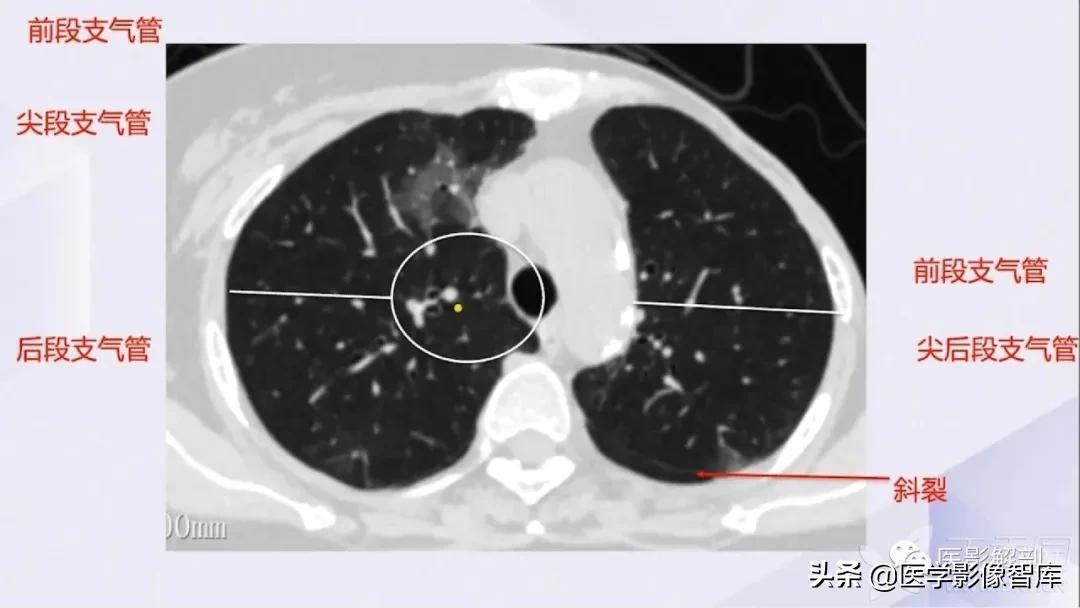

肺部CT解剖(高清图谱)